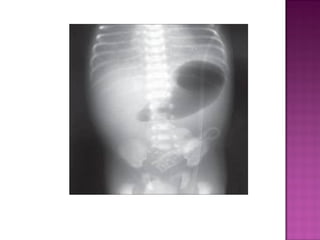

 Distention of stomach ,duodenum &

jejunum.

 Intestinal ischemiaduring intra uterine life.  Present with bilous vomitting & abdominal distention.

• 32.

 Distention ofstomach ,duodenum & jejunum.

 Due tointra uterine ischemic insult.  Bilous vomiting & distention.  Numerous dilated bowel loops.